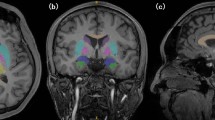

Linear regression analysis at P<0.001 FWE measuring the effect of WHtR on blood flow while controlling for age, predicts the most significant decreases as reported by voxel cluster size in the following five regions: Region 1 has an overall cluster size of 2666 voxels and includes the left superior temporal pole (coordinates −40, 16, –20; t=6.91), left frontal medial orbital cortex (coordinates −2, 30, –14; t=6.79) and left insular cortex (coordinates −28, 18, –16; and t=6.78). Region 2 has an overall cluster size of 207 voxels and includes the left frontal medial orbital cortex (coordinates −8, 56, –14; t=6.35) and right rectus (coordinates 8, 56, –18; t=6.35). Region 3 has an overall cluster size of 342 voxels and includes the right superior temporal pole (coordinates 48, 10, –14; t=6.23 and coordinates 32, 12, –32; t=7.10). Region 4 has an overall cluster size of 253 voxels at the left middle frontal cortex (coordinates −32, 54, 20; t=6.22). Region 5 has an overall cluster size of 90 voxels and includes the frontal superior right cortex (coordinates 14, −42, 52; t=6.17 and coordinates 18, 54, 42; t=5.96). Figure 3 illustrates these decreased areas of perfusion through transverse, coronal and sagittal slices. Furthermore, a plot of the regression slope of region 1 (left superior temporal pole and left frontal medial orbital cortex) demonstrates a negative correlation between WHtR and blood flow at P<0.001 FWE (Figures 4 and 5). This suggests that as body mass increases, the blood flow to both temporal pole and prefrontal cortex decreases.

Image sections showing regional cerebral blood flow (rCBF) decreases with elevated WHtR. Following a regression analysis of rCBF to WHtR, slices from coronal, sagittal and transverse sections show areas of significant hypometabolism: coronal, 035: right superior frontal cortex; right superior orbital frontal cortex; left middle frontal cortex; left superior medial frontal cortex; 045: right superior frontal cortex; left superior frontal cortex; left middle frontal cortex; 053: right superior frontal cortex; left precentral; left temporal pole; left medial inferior orbital frontal cortex; 061: right inferior orbital frontal cortex; left precentral; left temporal pole; left insula; left medial orbital frontal cortex; 079: left rolandic operculum ;left inferior temporal; right superior temporal pole. Sagittal, 058: right frontal inferior orbit; right putamen ; right superior temporal pole; right insula; 072: right mid frontal cortex right superior frontal cortex; 098: left medial orbital frontal cortex; left superior medial frontal cortex ;left medial orbital frontal cortex; 118: left mid frontal cortex; left superior frontal cortex; left temporal pole; 136: left precentral; left rolandic operculum ; left inferior temporal cortex; left superior temporal pole. Transverse; 059: right frontal superior cortex; left mid frontal cortex; 069: left superior frontal cortex; left rolandic operculum; 083: right mid frontal cortex; left mid frontal cortex; 109: right superior orbital cortex; left medial orbital frontal cortex; left temporal pole; left rolandic operculum; 117: right superior orbital frontal cortex, left medial orbital frontal cortex; left temporal pole, right superior temporal pole.